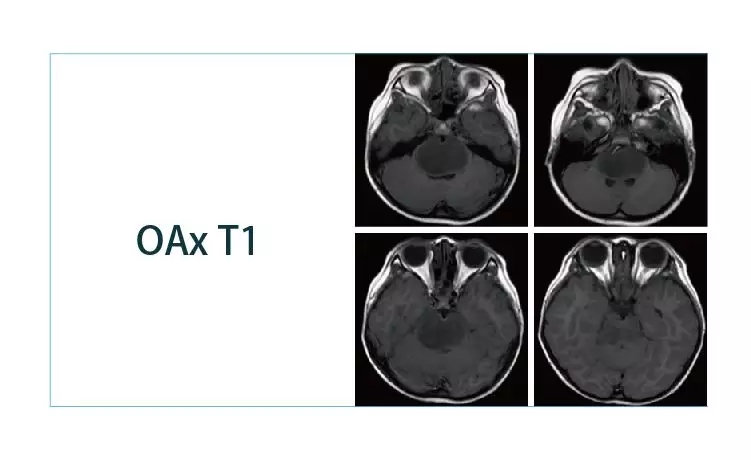

【朗润影像档案】20190329磁共振影像病例结果讨论